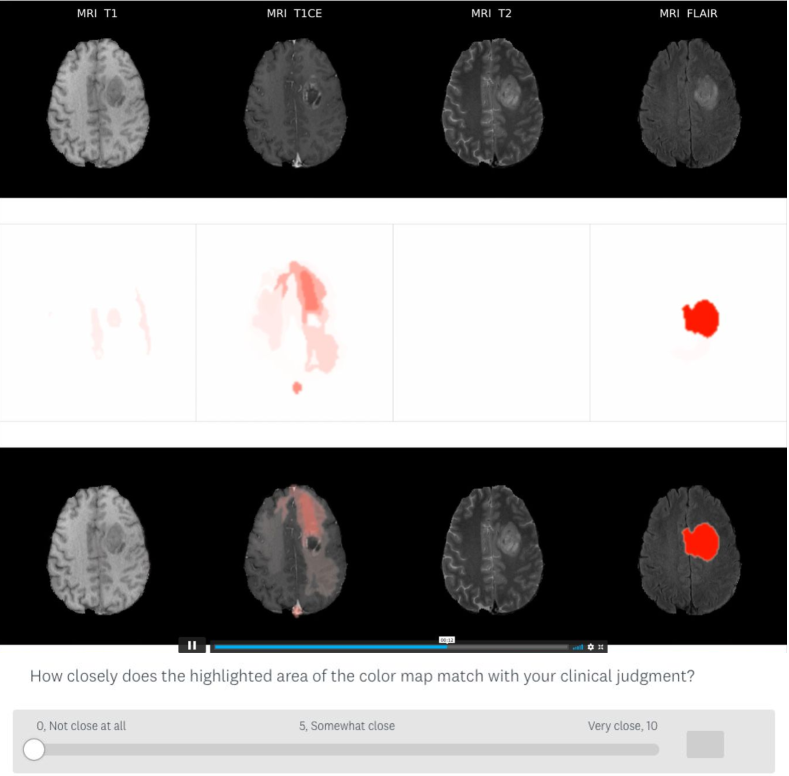

We conducted a user study including an online survey and an optional within-/post-survey interview with neurosurgeons. The survey, with a low-fidelity XAI system embedded to mimic XAI usage scenario in clinical decision support, asked neurosurgeons to interpret, comment, and rate the generated 3D multi-modal heatmaps (Fig. 1). Neurosurgeons rated the heatmaps regarding explanation plausibility, i.e.: “how closely the highlighted areas of the heatmap match with your clinical judgment?” The user study was approved by the Research Ethics Board of Simon Fraser University (Ethics No.: H20-03588). Six neurosurgeons were recruited and participated in the survey. Two of them participated in the optional interview. The survey lasted for 1 hour, and the interview lasted for 30 minutes. Details on the user study are in the Appendix.

Refer to caption

Figure 1: 3D heatmap (in video format) and questionnaire in the user study. Column: each MRI modality. Row: MRI, heatmap, and heatmap overlaid on MRI. Redness indicates the importance of that area for prediction.